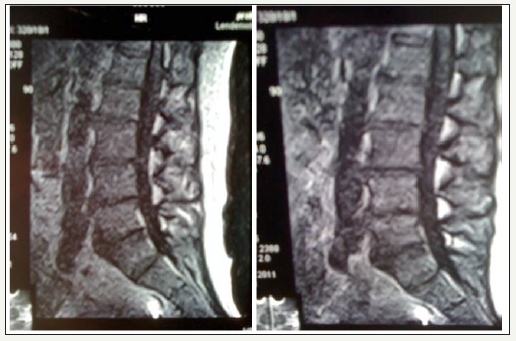

After alleviating the acute pain, a 3D vertebral column analysis and isometric force testing were carried out after about one week in all patients. The patients of groups 3 and 4 started wearing the Lumbar Stabilization Orthosis immediately after the first presentation. As an average wearing time of 6-8 hours per day, especially when standing and walking were agreed upon. In order to optically verify the influence of the lumbar spine stabilization orthosis on the body’s malformed statics, a Upright-MRI investigation of a 56 year old volunteer with known pseudoradicular lumbar pain was carried out experimentally. Morphologically, a significant correction of the lumbar hyperlordosis was observed with the stabilization orthosis in place. The lordosis angle without orthosis was? and with orthosis? Degrees (Figure 3).

figure 3: Example 56-year-old patient left and right with lumbar spine stabilization orthosis with a lower degree of hyperlordosis.